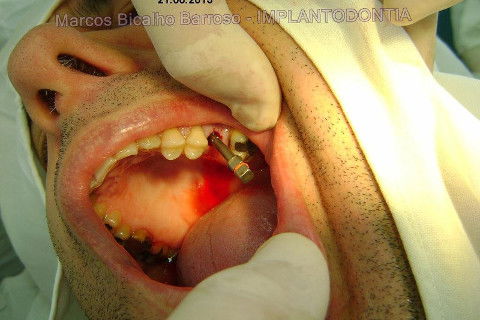

Instalação de um implante em região do 26. Utilizamos um implante cone morse Alvim Neodent 4.3 X 11,5. Foi uma cirurgia muito rápída e minimamente traumática, sem retalho e sutura.